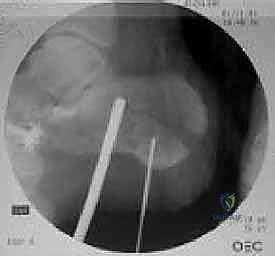

2. تقنية "عدم اللمس" (No-Touch Technique)

للحفاظ على حيوية الأنسجة الرقيقة (السديلة الجلدية)، يستخدم الدكتور هطيف أسلاك كيرشنر (K-wires) لرفع الجلد بعيداً عن مجال الرؤية دون استخدام مبعدات قاسية قد تدمر الأنسجة. هذه التقنية المتقدمة هي سر التئام الجروح السريع بدون نخر (Necrosis).

4. التثبيت المؤقت

يتم استخدام أسلاك معدنية دقيقة لتثبيت الشظايا في مكانها مؤقتاً، ثم يتم التحقق من دقة الرد باستخدام جهاز الأشعة السينية داخل غرفة العمليات (C-arm) لضمان عدم وجود أي انزياح ولو بمليمتر واحد.

صور إضافية من داخل غرفة العمليات توضح دقة الإجراء

توضح الصور التالية مدى تعقيد الجراحة والدقة التي يتطلبها تثبيت عظم الكعب، والتي يعكسها التميز الجراحي للأستاذ الدكتور محمد هطيف: